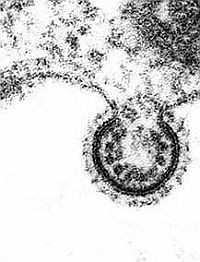

Az RSV (Respiratory syncytial virus), a csecsemőkben és kisgyerekekben előforduló alsó légúti vírusfertőzés gyerekkorban megnöveli az asztma kialakulásának kockázatát.

rsv-virus-d0000135A080109d8674d